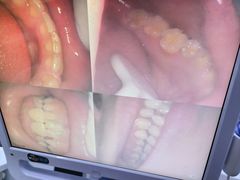

• 好牙依口腔(开源店)

• 全部图片

• -好牙依口腔(开源店)

叶小小小小屁 | 25-05-22